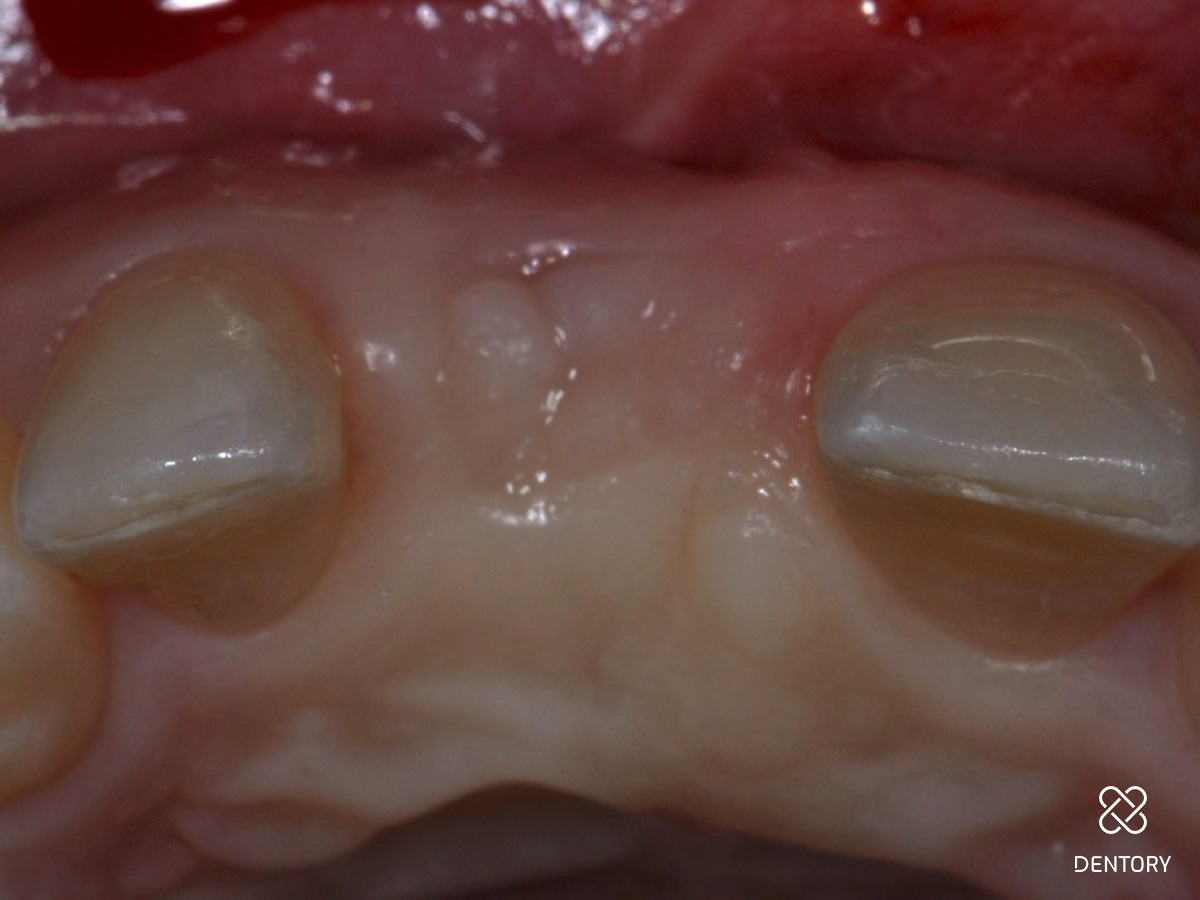

Abbildung 17

Heilung: 8 Wochen Post-OP - frontale Ansicht

Abbildung 18

Heilung: 8 Wochen Post-OP - okklusale Ansicht